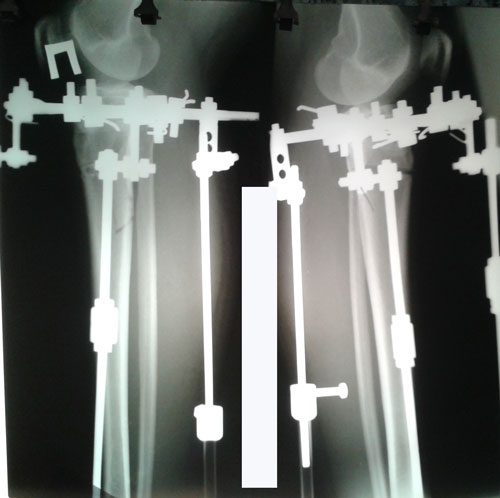

Дата операции 14.07.2017г.

Дата снятия аппаратов 25.09.2017г.

Срок лечения 70 дней.